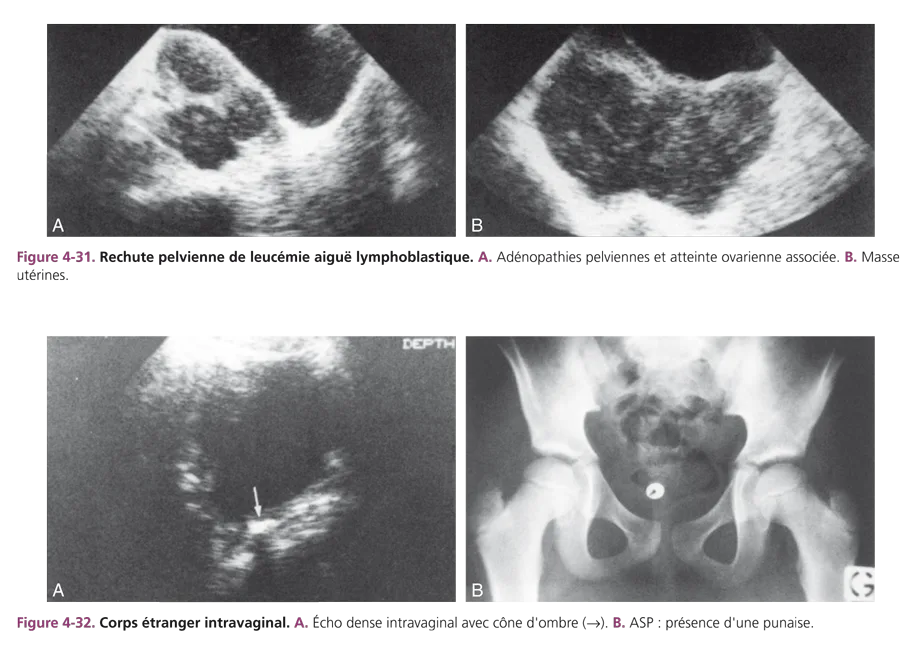

Adénopathies tumorales pelviennes

Elles se présentent comme des masses rondes, homogènes, très hypoéchogènes. Elles sont à rechercher lors des rechutes de leucose aiguë. Cette rechute peut intéresser également les ovaires et l’utérus (fig. 4-31). Cette atteinte est méconnue chez la fille alors que la classique rechute testiculaire des garçons est cliniquement évidente.

Au cours des lymphomes non hodgkiniens, les adénopathies iliaques s’associent à une masse iléocæcale et fréquemment à une ascite dont la ponction fait le diagnostic.